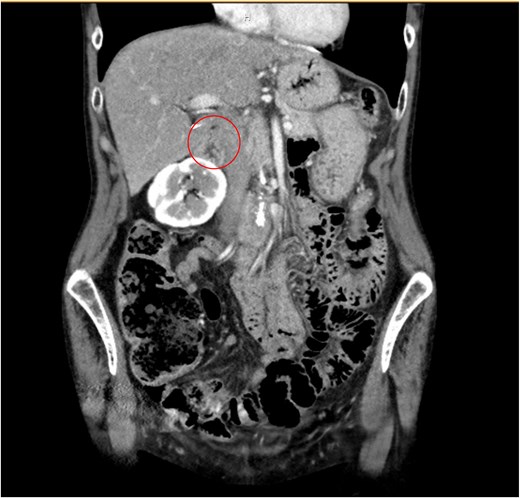

A 62-year-old female was found to have an incidental 1.3 cm right adrenal mass on computed tomography (CT) imaging, which was completed for suspected colitis (Fig. 1). The patient’s medical history was significant for hypertension. Following resolution of acute pathology, the patient was evaluated by endocrine surgery. During evaluation the patient denied episodic headaches and diaphoresis, weight loss, weight gain, and abdominal pain. Next, the functional status of the mass was evaluated given a history of poorly controlled hypertension despite three anti-hypertensives. The workup revealed elevated norepinephrine (1092 pg/ml), dopamine (37 pg/ml), and plasma catecholamine (1156 pg/ml). Low dose overnight dexamethasone suppression test showed slightly elevated cortisol level of 2 μg/dl. The serum renin/aldosterone, and urine metanephrine were normal. Given the concern for a functional adrenal adenoma, the patient was counseled on the risks and benefits of surgery, and it was recommended that she undergo a right adrenalectomy. Prior to surgery, the patient was evaluated by endocrinology and was pre-medicated with prazosin for 10 days followed by metoprolol.

Coronal CT of abdomen and pelvis noting a 1.3 cm right adrenal mass (circle).